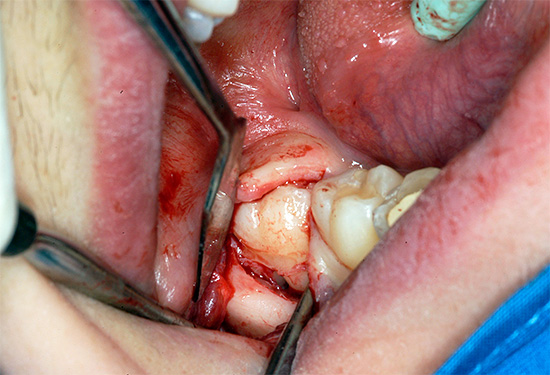

Foto dei denti del giudizio rimossi:

Nella foto - un dente del giudizio rimosso in alcune parti:

Qualsiasi dentizione difficile del dente del giudizio con dolore alla gengiva e ai tessuti circostanti richiede una diagnostica a raggi X. Per determinare la posizione del dente nella mascella (angolo di inclinazione, struttura, forma), viene utilizzato un ortopantomogramma (OPTG) o un'immagine panoramica di tutti i denti su entrambe le mascelle.